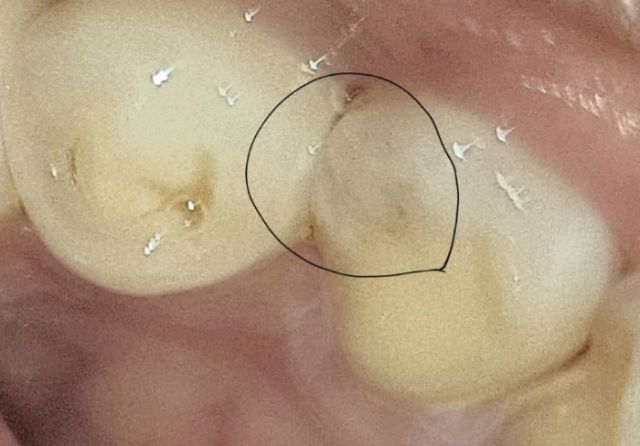

이거 충치인가요?? 답변 부탁드립니다

치아사진 찍었다가 우연찮게 저렇게 검은얼룩을 봤는데

저게 충치인가요? 치과는 내일 가볼려고요 충치면 어느정도 심각한건가요???

사진이 흐려 확실하지는 않지만 충치일 가능성이 높습니다. 치아와 치아 사이 부위에 충치가 생긴 것으로 보입니다. 치과에 가서 검사 받아야 합니다.

사진상으로는 충치는 아닌거 같고 잇몸사이에 치석이 잇는거 같으니 치과에 가셔서 스켈링을 받아보세요.

조금 애매한 것 같습니다. 엑스레이 촬영을 해봐야 명확히 알 수 있어보이며 치과는 가보시는 게 좋겠습니다.

얼룩 자체는 사진으로 봤을때 충치의 양상은 아닌 것으로 보입니다. 충치라 하더라도 그렇게 심하진 않을 것 같습니다.